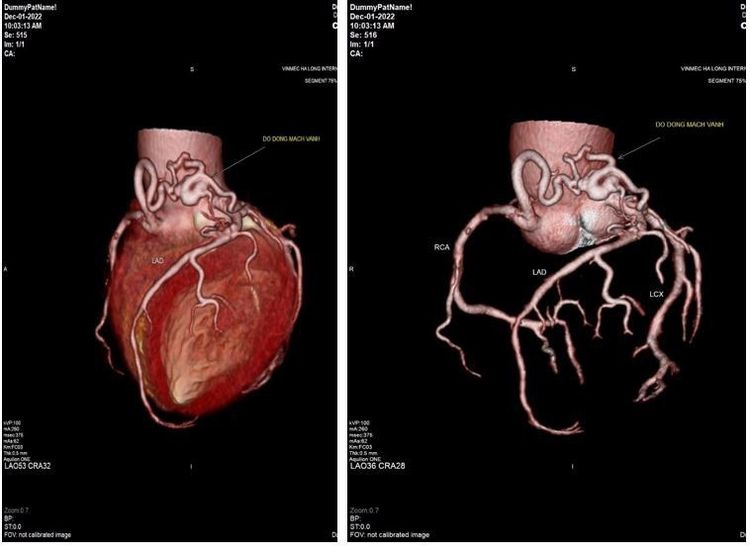

Phát hiện tình trạng dò động mạch vành cho người bệnh không thể siêu âm tim gắng sức

Ông N. 62 tuổi có tiền sử đái tháo đường tuýp 2 đã được 5 năm, đang điều trị đều nhưng gần đây có biểu hiện tức ngực, khó thở nhẹ khi gắng sức. Khi vào Bệnh viện Vinmec Hải Phòng thăm khám, ông được làm các xét nghiệm về men tim, siêu âm tim và điện tim để khảo sát động mạch vành nhưng không thấy bất thường. Do thoái hóa khớp, người bệnh không thể chạy để làm nghiệm pháp gắng sức điện tâm đồ nhằm phát hiện xem có tình trạng thiếu hụt máu cung cấp cho cơ tim không.

Vậy đâu là giải pháp để khảo sát được kỹ càng cho trường hợp này? Các bác sĩ khoa Tim mạch, Bệnh viện ĐKQT Vinmec Hải Phòng đã chỉ định tiếp tục chụp MSCT động mạch vành. Kết quả là phát hiện được bất thường có dò động mạch vành vào động mạch phổi.

Tiếp tục đánh giá các yếu tố nguy cơ tim mạch trong 10 năm tới với người bệnh, các bác sĩ đề xuất hiện tại ông có thể điều trị nội khoa, kiểm soát các yếu tố nguy cơ như huyết áp, đường máu và mỡ máu, nhưng hàng tháng cần siêu âm để đánh giá chức năng tim. Khi đó, nếu diễn biến nặng hơn thì sẽ tiến hành can thiệp để đảm bảo an toàn.

Như vậy, trong trường hợp này, MSCT là phương tiện hiệu quả giúp bác sĩ tránh được việc chẩn đoán bỏ sót cho người bệnh. “Dò động mạch vành vào các buồng tim là một bệnh lý tim bẩm sinh hiếm gặp, biểu hiện không rõ ràng. Siêu âm tim có vai trò quan trọng trong sàng lọc bệnh lý này. Tuy nhiên những trường hợp kín đáo, khó phát hiện thì phải cần đến vai trò của MSCT động mạch vành. Bởi MSCT có thể đánh giá được hình thái cũng như các bất thường xơ vữa hẹp của động mạch vành, cung cấp nhiều thông tin cho chỉ định điều trị can thiệp và theo dõi bệnh. Do một sốt rối loạn bẩm sinh của tim như dò động mạch vành, phình giãn động mạch vành cũng làm rối loạn dòng chảy trong lòng động mạch vành có thể gây nên các triệu chứng tức ngực, khó thở khi gắng sức. – ThS.BS Trần Văn Quý – Trưởng Khoa Khám bệnh và nội khoa, Bệnh viện ĐKQT Vinmec Hải Phòng cho biết.